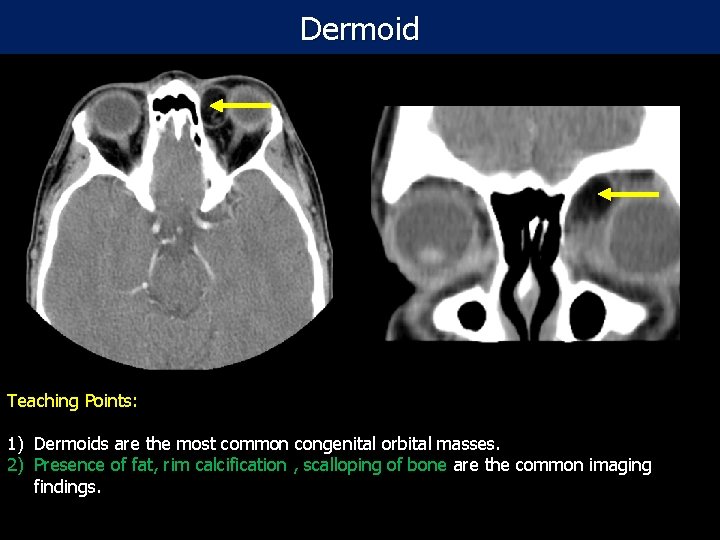

Dermoid Teaching Points: Post- contrast CT scan of the orbit in 28 year old female: Oval-shaped fat density lesion 1) Dermoids are the most common congenital orbital masses. in the medial canthus of the left orbit with no enhancement or bony erosion consistent 2) Presence of fat, rim calcification , scalloping of bone are the common imaging with dermoid tumor findings.